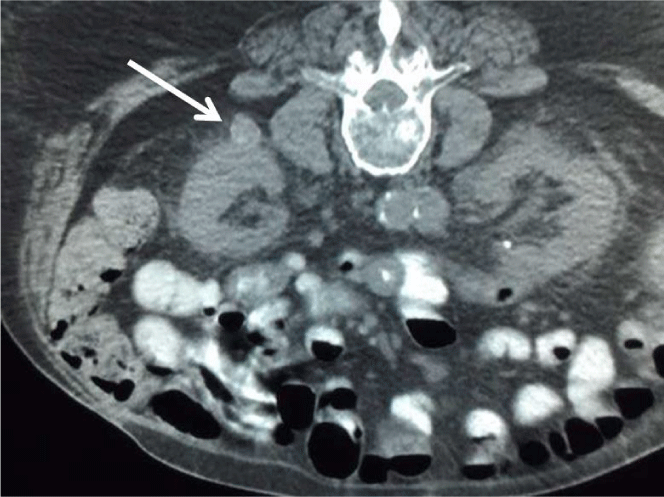

A new ablation probe was then used for the procedure. A 13-gauge needle was used to gain access into the left renal lesion. Through this introducer, 20 cm microwave ablation PR probe was advanced into the lesion. The left renal lesion was ablated for 7 minutes at 65 W; CT imaging during the ablation demonstrated ablation probe in good position (Figure 6). Post ablation CT demonstrated air density within the left renal lesion consistent with successful ablation (Figure 7). Additionally, there has been marked interval decrease in left flank subcutaneous and left perinephric air.

Figure 6: After evacuation of gas, a 17-gauge microwave ablation probe placed in the left renal tumor (arrow).

Figure 7: After ablation of the tumor, CT scan of the abdomen shows shrinkage of the tumor with typical post-ablation intra- and peri-tumoral gaseous density (arrow). Note the significant interval resolution of the subcutaneous and retroperitoneal gas.